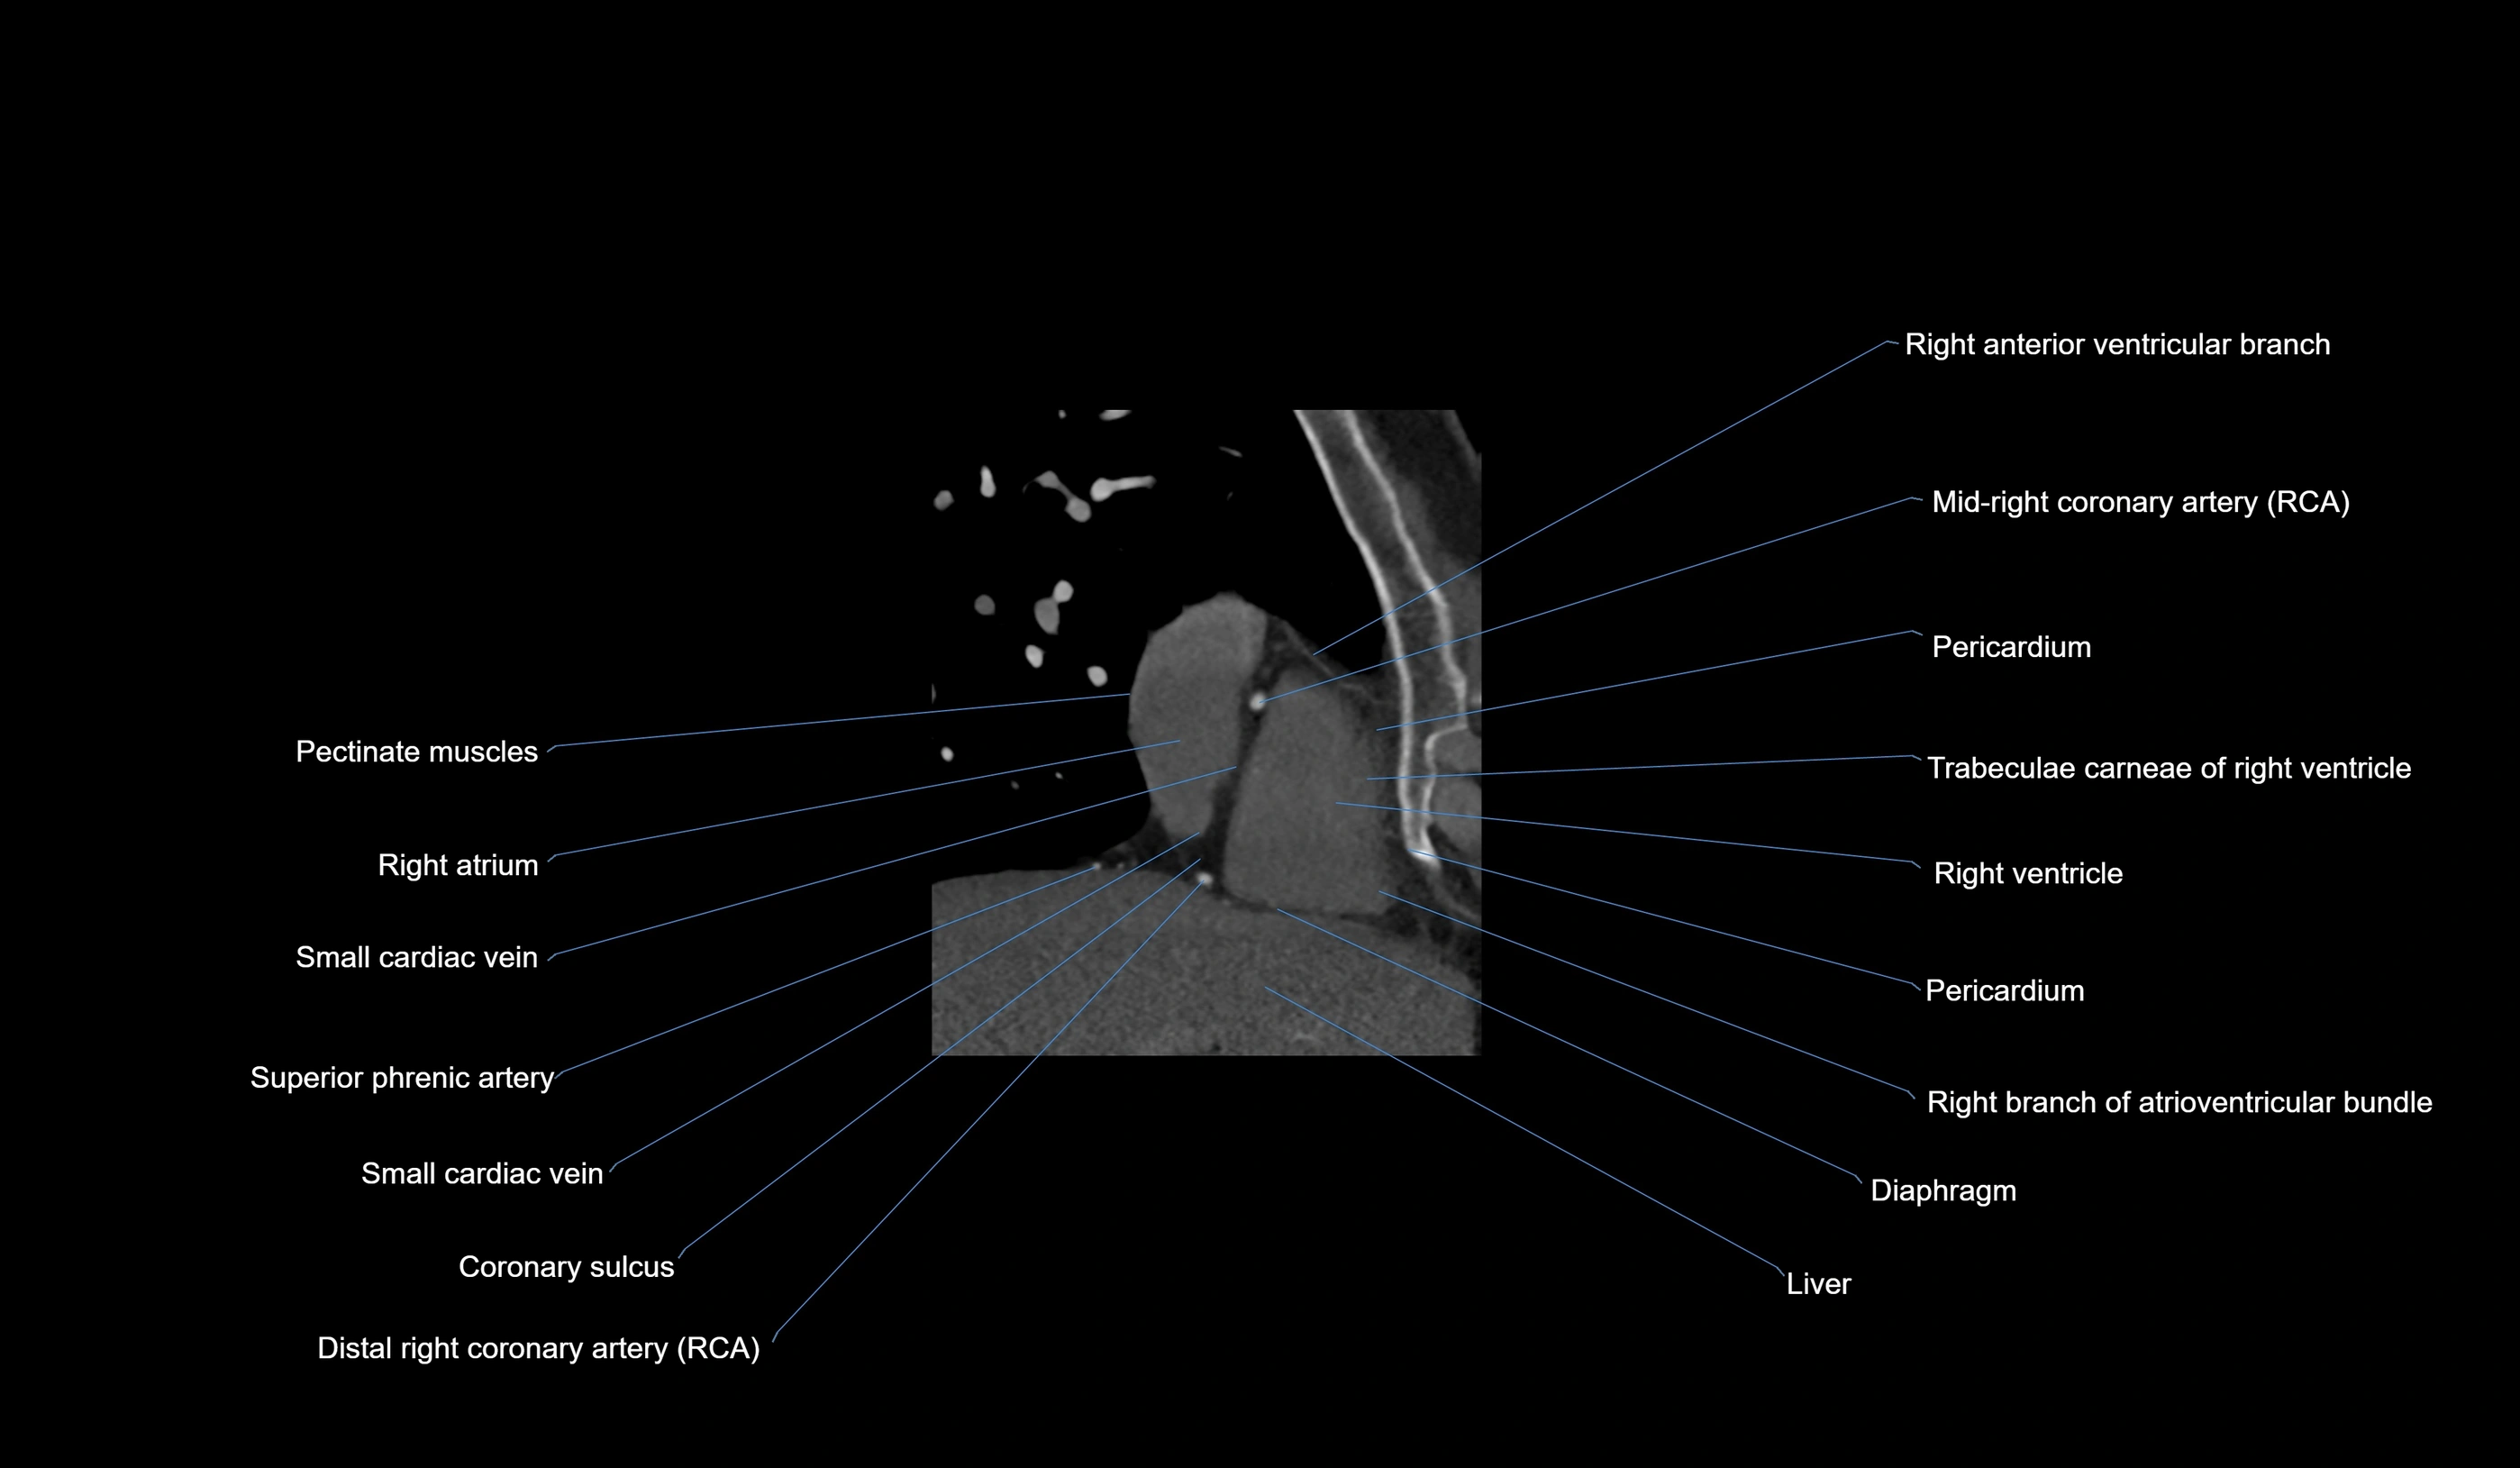

CT Coronary Angiography (CCTA):

Best non-invasive modality for acute marginal artery visualization

Shows origin, course along the acute margin, and right ventricular branches

Detects stenosis, occlusion, calcified and non-calcified plaques, aneurysm, or anomalous course

Multiplanar reformats and 3D reconstructions help in pre-PCI and surgical planning

Critical for assessing right ventricular infarction risk in RCA disease